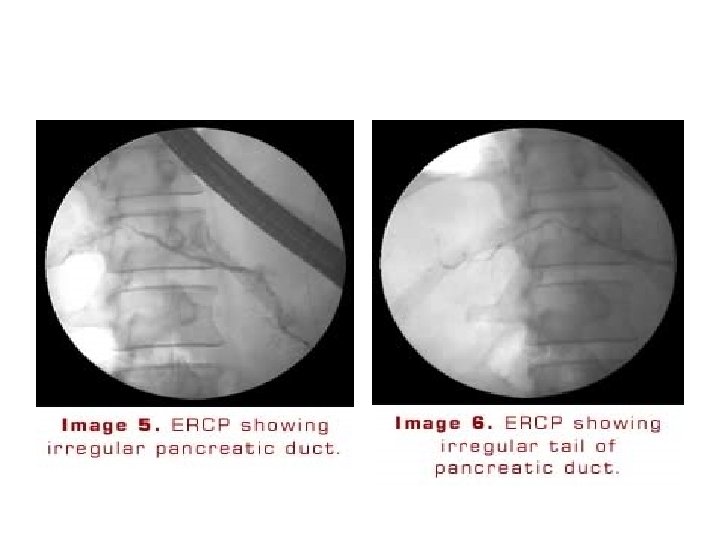

ERCP • May provide useful information on the status of the pancreatic ductal system • Abnormalities include : • 1)luminal narowing • 2)irregularities in the ductal system with stenosis, dilation, saculation, and ectasia • 3)blockage of the duct by calcium deposits Endoscopic ultrasonography • The most predictive endosonographic feature is the presence of stone